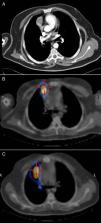

Upon physical examination, the patient was asymptomatic. Workup values showed: prolactin, 139ng/ml; total testosterone total 1.16ng/ml; free testosterone 3.41pg/ml; PTH 2.112pg/ml; gastrin, >1050pg/ml; calcium, 11.2mg/dl; phosphorus 2.82mg/dl. Computed tomography (CT) revealed a 3-cm solid mass with intravenous contrast uptake in the anterior mediastinum in contact with the pleura and right pericardium near the homolateral auricle, with no calcifications or cavitations (Fig. 1A). Octreotide scan detected 2 nodular lesions with elevated high somatostatin receptor density: one in the right hemithorax and the second at the tail of the pancreas. SPECT/CT confirmed the location of both lesions (Fig. 1B).

During outpatient follow-up, SPECT/CT in October 2007 showed increased uptake in the right paramediastinal region (Fig. 1C). CT confirmed the presence of an anterior mediastinal consolidation with pseudo-nodular morphology in contact with the pleura and the right pericardium and proximal to the ipsilateral auricle. In February 2008, the patient once again underwent surgery, specifically right thoracotomy, with no observation or palpation of any nodules; therefore, part of the pericardium was resected as well as the area of fibrosis that had been theoretically located by increased uptake during scintigraphy. The anatomic pathology study reported no evidence of neoplasm and the diagnosis was radiation fibrosis. Currently, the patient is disease-free and continues in oncologic follow-up including annual CT.